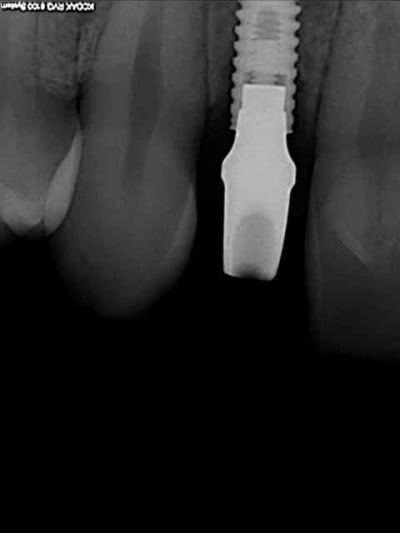

tes implants 12 et 13 n'ont pas le même niveau d'enfouissement, tu n'as pas peur d'une lyse osseuse de 13 pour venir au niveau du col de 12 ?

je reviens sur ce cas que j'ai un peu délaissé...

-cicatrisation

-mise en place vis de cica petit diamètre

-ensuite on augmente le diamètre en conservant et en gonflant les tissus gingivaux